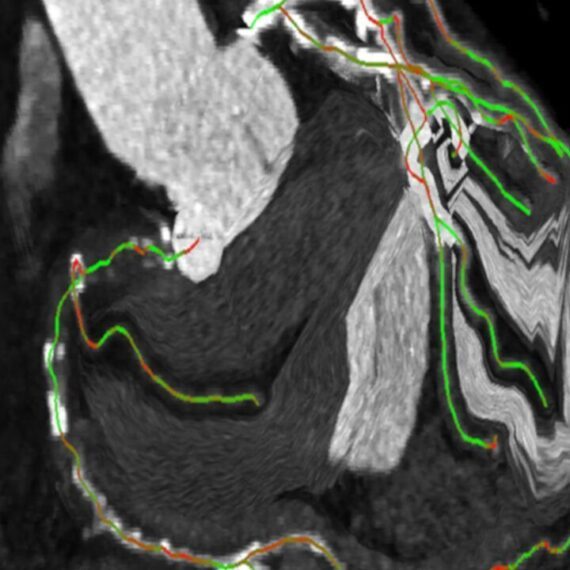

- Автоматическая сегментация коронарных окклюзий, определение и цветовое кодирование центральных линий.

- Цветовая кодировка указывает ракурс сегмента сосуда. Это позволяет выбрать оптимальный угол сегмента поражения, который обычно не виден на рентгенограмме до фактического начала процедуры.

- Кодированные цветом центральные линии используются для регистрации во время процедуры. Таким образом, требуется меньше ангиографических изображений.

При интервенционном вмешательстве CTO syngo CTO Guidance упрощает процедуры позиционирования проводника, обеспечивая параллельный (рентгеноскопические и КТА изображения) контроль. Дополнительная информация, такая как данные о кальцификации и истинная длина областей тромбированных сосудов, помогает правильно выбрать проводник, ориентацию и успешно провести операцию.